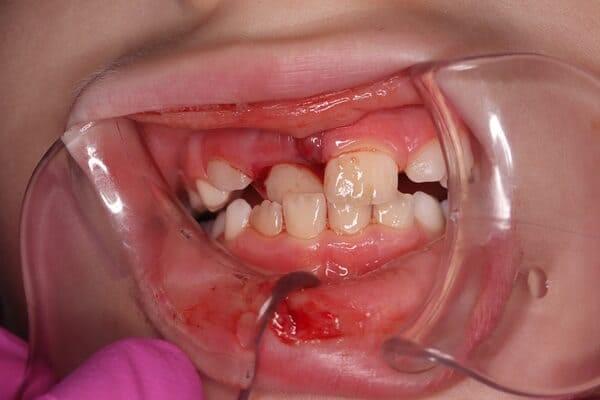

Дівчинка 2 років, але зуби вже мають глибокі ураження із залученням у запальний процес пульпи (“нерва”) зуба. На жаль, так трапляється і зволікати в такому випадку не можна. Було проведено лікування в умовах анестезіологічного забезпечення під контролем досвідченої анестезіологічної команди. Передні зубчики відновлено естетичними коронками, на жувальних зубчиках проведена герметизація фісур, а один вже має глибоке ураження карієсом, тому теж покритий коронкою. Одразу після лікування ясна можуть виглядати дещо травмованими, але за кілька днів вони повністю відновляться.